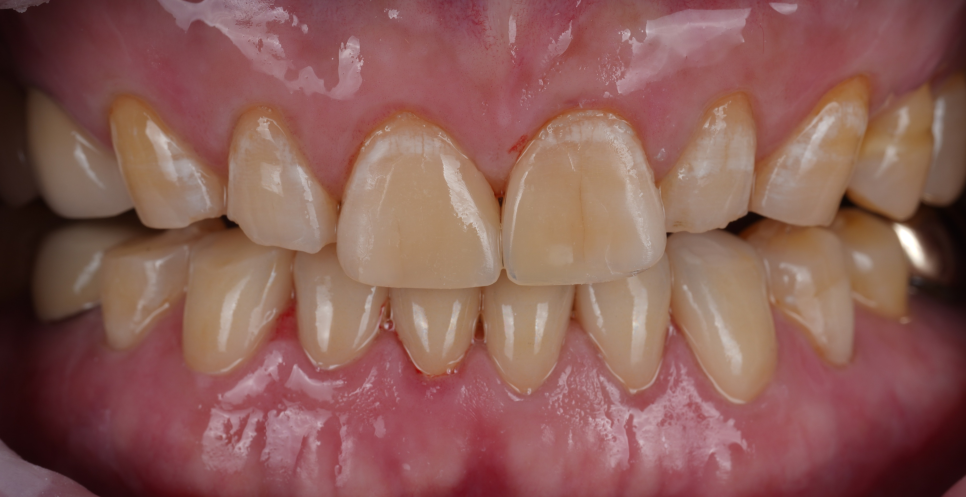

기능·심미 둘 다 회복된 안정적인 상태

촬영일 : 251029

본래 길이를 되찾았고 주변 치아와도 조화롭게 잘 어우러져 일상생활에서 어색함 없이 사용하실 수 있는 상태가 되었어요.

'이렇게 감쪽같이 되는 거면 더 빨리할 걸 그랬다.'라고 말씀해 주셨습니다ㅎㅎ

촬영일 : 251013 / 251029